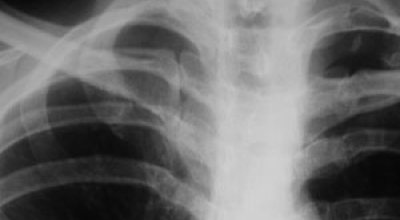

- Рентгеновская диагностика. Используя низкочастотные излучения, рентген делает видимыми кости, но распознавание трещин костей может быть затруднено. Рентгеновские лучи также полезны при диагностировании повреждений легких.

Чтобы определить трещину в ребре, необходимо провести рентгенологическое исследование. На основании снимка специалист выявляет место, где локализуется повреждение. По рентгенологическому фото врач также получает информацию о характере травмы.

Фото снимка при переломе ребер: